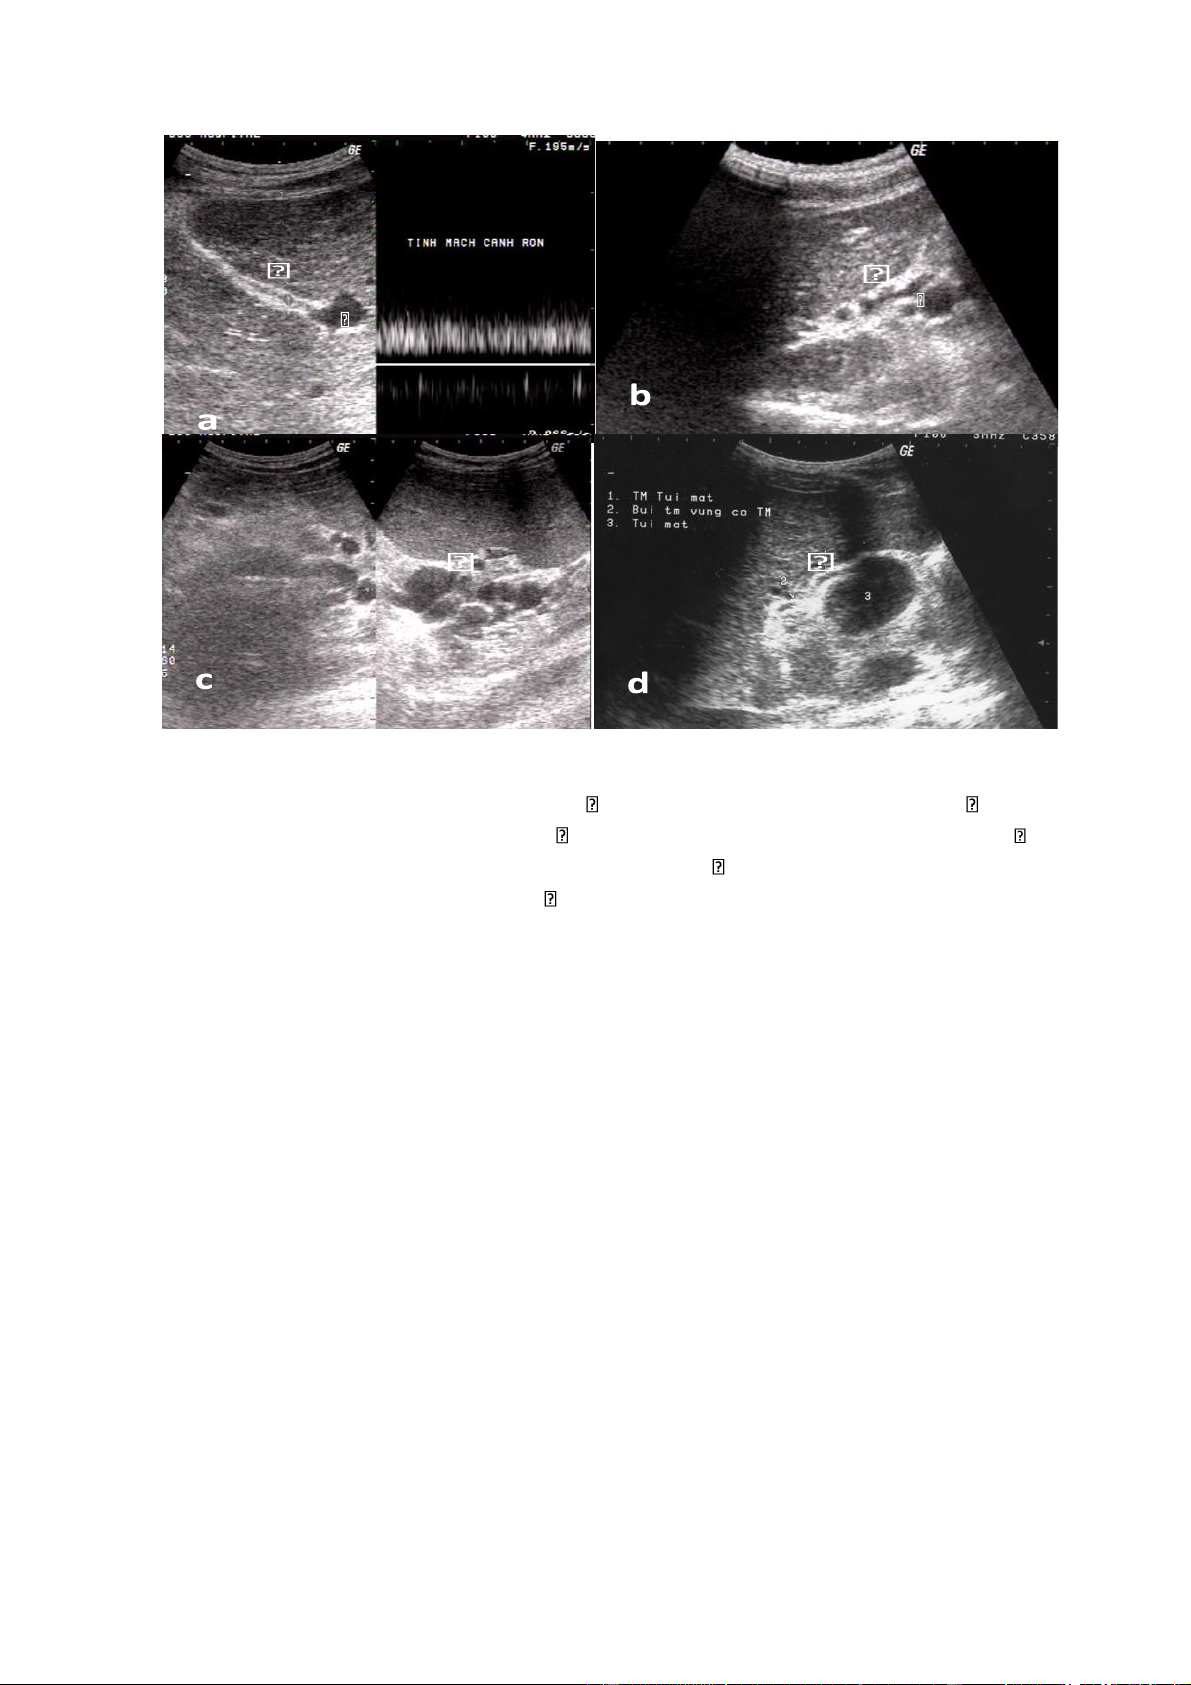

Hình 5.3.. Các đường đổi dòng cửa-chủ:

a. Tái lập tĩnh mạch cạnh rốn ( ) bắt đầu từ nhánh trái tĩnh mạch cửa ( )

b. Tĩnh mạch vành vị giãn ( ): hợp lưu tĩnh mạch lách-mạc treo tràng trên ( );

c. Tĩnh mạch vùng rốn lách giãn thành búi ( )

d. Tĩnh mạch túi mật giãn ) -

Các đường đổi dòng cửa-chủ biểu hiện các dấu hiệu sau:

+Tái lập tĩnh mạch cạnh rốn

+ Đổi dòng sang tĩnh mạch vành vị làm tĩnh mạch này giãn

+Đổi dòng qua các tĩnh mạch lách-thận. Trong trường hợp này tĩnh mạch

thận trái thường giãn. Sự đổi dòng này gặp trong khoảng 48% các trường hợp tăng

áp lực tĩnh mạch cửa. Trên siêu âm thường thấy tĩnh mạch vùng rốn lách giãn thành

búi ngoăn ngoèo, có thể thấy tĩnh mạch quanh thận trái và tĩnh mạch thận trái giãn.

+ Ngoài ra, tăng áp lực tĩnh mạch cửa có thể có các đổi dòng sang tĩnh mạch

mạc treo tràng dưới nối với tĩnh mạch chủ dưới qua hệ thống tĩnh mạch trực tràng,

qua phúc mạc nối hệ thống cửa và tĩnh mạch chủ dưới, vòng nối xuyên qua gan,

qua bao gan để nối với các tĩnh mạch phúc mạc. Các tĩnh mach cửa phụ của các dây

chằng treo gan có thể phát triển, chúng là những vòng nối liên gan và cơ hoành. -

Giãn tĩnh mạch túi mật. -